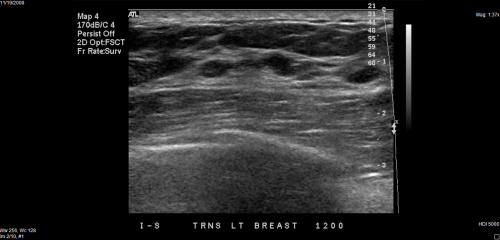

Destounis and colleagues reviewed the performance of screening ultrasound at their site in women with heterogeneously dense or extremely dense breast tissue, using data from 14,548 exams performed between 2013 and 2016. They compared the performance of screening ultrasound year to year.